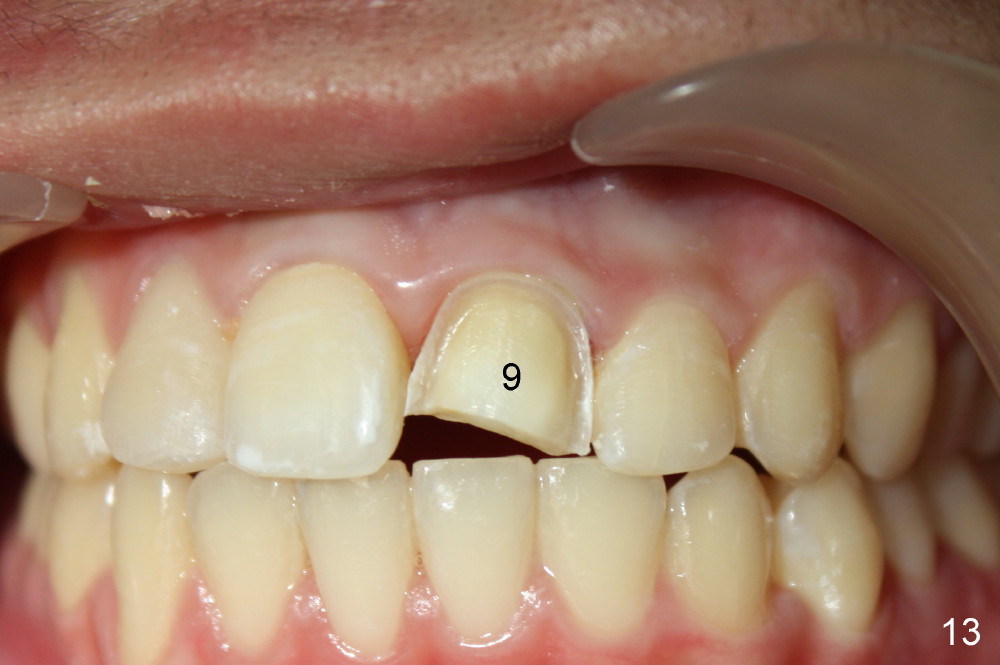

Two weeks later, the shade of #9 was similar to that of #10 (Fig.11). Composite with the lightest shades were used to finish build up (Fig.12 *). The tooth #9 was prepared for veneer; the dentine looks pretty light (Fig.13). Proper shade was chosen (Fig.14). Veneer at the site of #9 is bonded (Fig.15). The patient returns for excess cement removal 1 week post cementation (Fig.16).